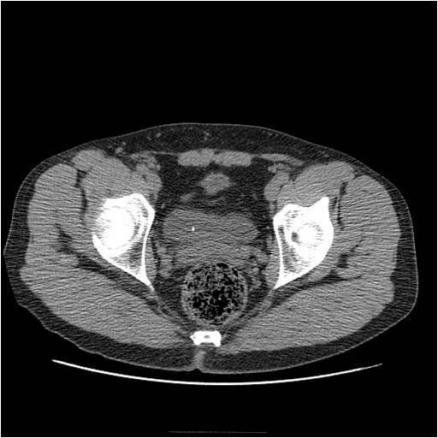

Scanner TDM sans injection à basse dose. Calcul millimétrique enclavé au niveau du méat urétéral droit dans le cadre d’une colique néphrétique droite. Le scanner est maintenant utilisé de façon courante en urgence pour la prise en charge des patients avec une douleur du flanc. Cette stratégie s’est imposée par sa simplicité et sa rapidité, puisqu’elle remplace par un examen unique sans injection de produit de contraste les autres techniques (ASP, échographie et UIV) permettant une prise en charge rapide de ces patients.